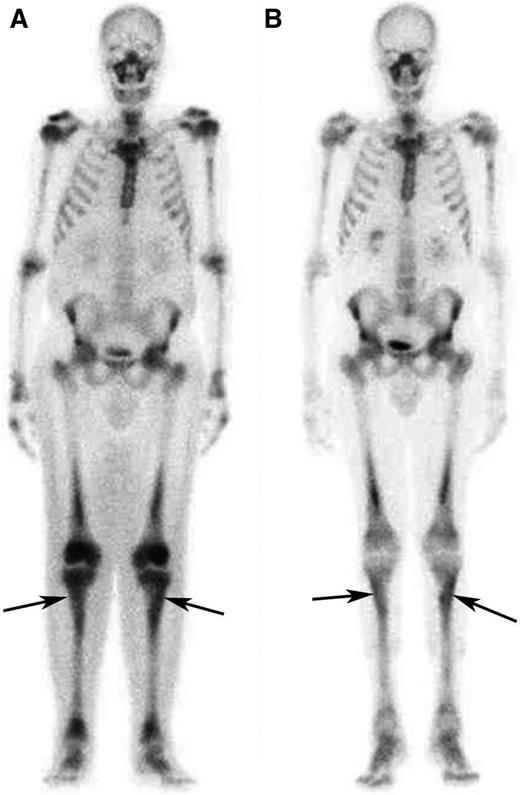

Response to treatment in the long bones assessed by bone scintigraphy. (A) Whole-body 99Tc-bone scintigraphy performed before treatment and (B) after 12 months of treatment with SRL and PDN in patient #5. The scans show a significant reduction in tracer uptake especially in long bones such as the tibias (arrows) and the femurs.

The remaining 8 patients showed PRs of at least one involved site. Retroperitoneal lesions regressed partially in 4/8 cases and completely in 1/8 (Figure 1 and supplemental Figure 2): at last follow-up, only 2 patients had double-J ureteral stents, and the patient with repeat bowel obstructions (patient #1) no longer developed such complications. Cardiovascular lesions improved in 3/4 cases: the 2 patients with severe pericarditis (one of whom was previously described28 ) underwent pericardiocentesis and remained free of pericardial effusion over the entire follow-up (Figure 1). Bone disease usually remained stable, although an improvement at 99Tc-scintigraphy was observed in 3 cases (Figure 2). CNS lesions progressed in patient #6 and stabilized in patient #3, whereas in patient #7 there was no recurrence of the surgically excised brain mass, and the remaining nodules showed partial regression (supplemental Figure 3). Lung involvement stabilized in all cases. The outcome of the remaining disease manifestations is reported in Table 2. Systemic symptoms improved in most patients; the only patient who experienced persistent systemic manifestations was patient #8. C-reactive protein levels also tended to decrease over time (supplemental Figure 4).